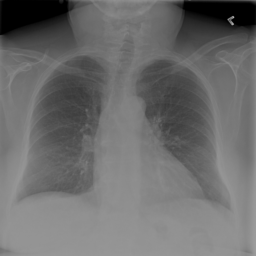

Anomaly detection is the problem of recognizing abnormal inputs based on the seen examples of normal data. Despite recent advances of deep learning in recognizing image anomalies, these methods still prove incapable of handling complex medical images, such as barely visible abnormalities in chest X-rays and metastases in lymph nodes. To address this problem, we introduce a new powerful method of image anomaly detection. It relies on the classical autoencoder approach with a re-designed training pipeline to handle high-resolution, complex images and a robust way of computing an image abnormality score. We revisit the very problem statement of fully unsupervised anomaly detection, where no abnormal examples at all are provided during the model setup. We propose to relax this unrealistic assumption by using a very small number of anomalies of confined variability merely to initiate the search of hyperparameters of the model. We evaluate our solution on natural image datasets with a known benchmark, as well as on two medical datasets containing radiology and digital pathology images. The proposed approach suggests a new strong baseline for image anomaly detection and outperforms state-of-the-art approaches in complex medical image analysis tasks.

翻译:异常检测是根据正常数据实例识别异常输入的问题。尽管在识别图像异常方面最近取得了深层次学习的进展,但这些方法仍然证明无法处理复杂的医学图像,如胸部X光几乎看不到异常和淋巴节点转移等。为了解决这一问题,我们引入了一种新的强有力的图像异常检测方法。它依靠古典的自动解剖器方法,经过重新设计的培训管道来处理高分辨率、复杂图像和图像异常分数。我们重新审视了完全不受监督的异常点检测的非常问题说明,在模型设置期间,根本没有提供异常的例子。我们提议放松这一不现实的假设,仅使用少量有限的异常点来开始搜索模型的超参数。我们评估我们使用已知基准的天然图像数据集以及包含放射学和数字病理图像的两个医疗数据集的解决方案。拟议方法为在复杂的医学图像分析任务中,为图像异常点检测和超常规状态方法提供了新的强基线。